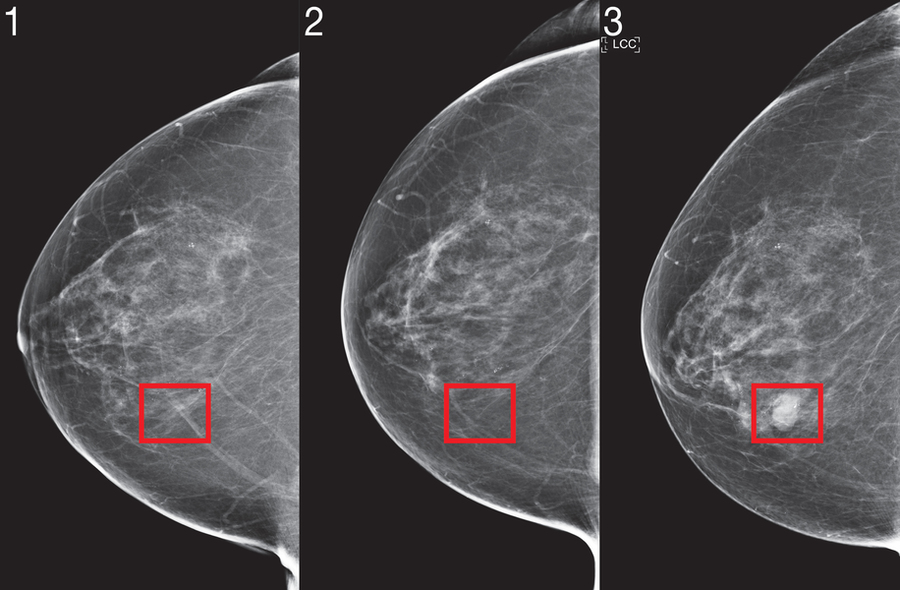

两年前,由麻省理工学院计算机科学与人工智能实验室(CSAIL)和杰米尔诊所(J-Clinic)组成的科学家团队展示了一种深度学习系统,可以仅使用患者的乳房X线照片来预测癌症风险。该模型给我们巨大的希望,尤其是该模型具有更高的包容性:白人和黑人妇女都同样准确。这一点特别重要,因为黑人妇女死于乳腺癌的可能性增加了43%。

为此,他们量身定制了新的“ Mirai”算法,以捕捉风险建模的独特要求。Mirai联合模拟了多个未来时间点的患者风险,并且可以选择受益于年龄或家族病史等临床风险因素(如果有)。该算法还设计用于产生在临床环境中较小差异之间一致的预测,例如乳腺X线摄影机的选择。

该团队在先前的工作中对来自马萨诸塞州总医院(MGH)的200,000多个考试的相同数据集进行了Mirai培训,并在MGH,瑞典卡罗林斯卡研究所和台湾长庚纪念医院的测试仪上对Mirai进行了验证。Mirai现在已安装在MGH,团队的合作者正在积极致力于将模型整合到护理中。

在所有三个数据集中,Mirai在预测癌症风险和识别高风险人群方面比以前的方法准确得多。在比较MGH测试集上的高风险人群时,研究小组发现,与目前的临床标准Tyrer-Cuzick模型相比,他们的模型确定的未来癌症诊断要多出将近两倍。在MGH测试集中不同种族,年龄组和乳房密度类别的患者以及在Karolinska测试集中不同癌症亚型的患者,Mirai的准确性相似。

最近,基于深度学习乳腺摄影的风险模型显示出令人鼓舞的性能。为了将这项技术带入临床,研究团队确定了他们认为对风险建模至关重要的三项创新:联合建模时间,可选使用非图像风险因素以及确保在整个临床环境中保持一致性能的方法。